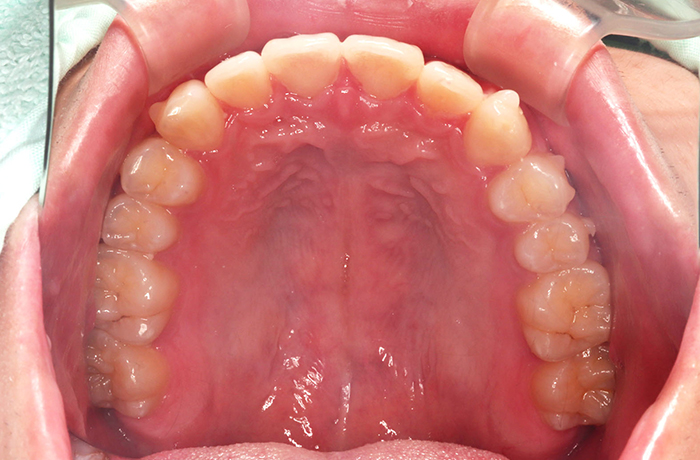

治療後

after

患者の症状 叢生、正中のずれ、上顎左右側切歯の口蓋側転位(交叉咬合)

治療方法 非抜歯で、マウスピース型カスタムメイド矯正歯科装置(インビザライン)による矯正

歯列弓を拡大することで非抜歯を可能にしました。

治療結果 側切歯の交叉咬合は解消、上下正中のずれも改善し咬み合わせが良くなりました。